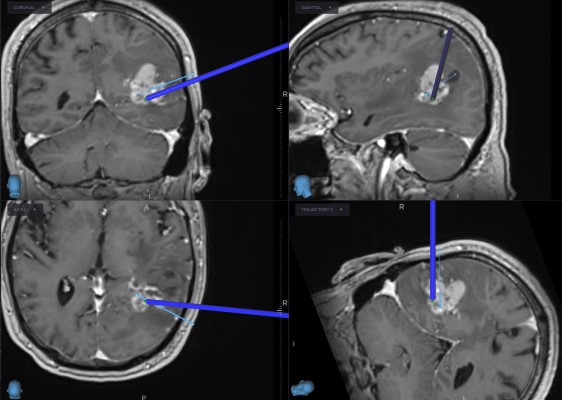

This is a 69 year old male with a known history of renal cell carcinoma who presented with cognitive decline and a neck mass.He had memory issues which were attributed to chemotherapy. He also was having new headaches. The neck mass was due to an infection. Neurologic examination was relatively unremarkable.